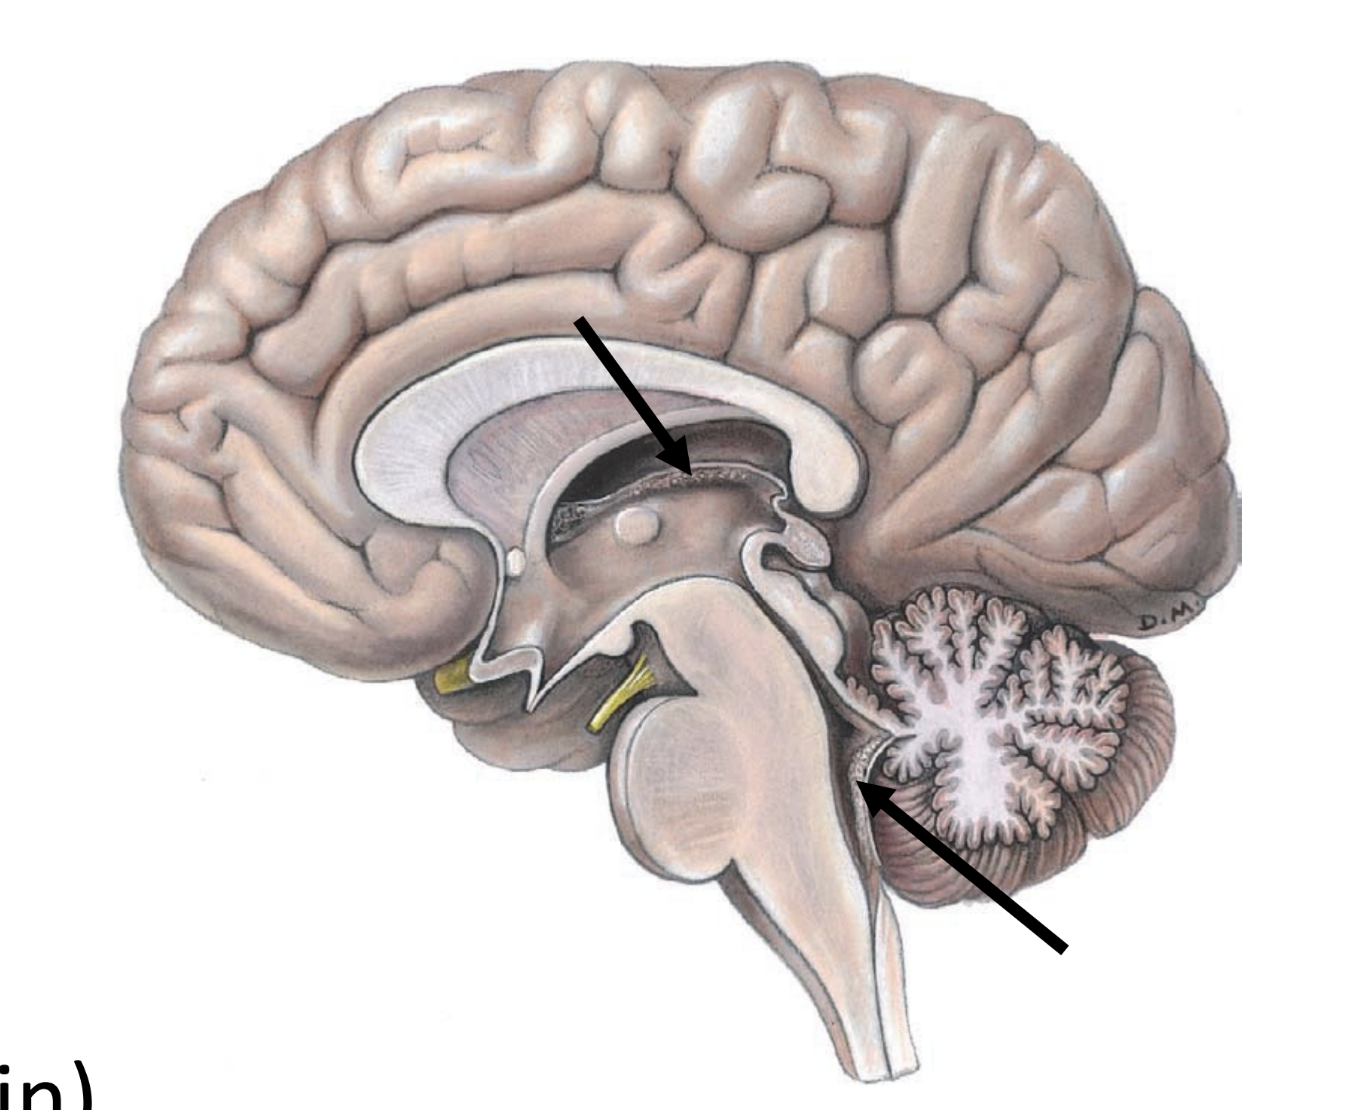

subarachnoid space

located between arachnoid and pia mater

• contains cerebrospinal fluid (csf) — ultrafiltrate of plasma produced in ventricles of the brain

• characteristics: clear, colorless, odorless

• cushions brain

• provides nourishment to and carries waste away from CNS

<p>located between arachnoid and pia mater</p><ul><li><p>contains cerebrospinal fluid (csf) — ultrafiltrate of plasma produced in ventricles of the brain</p></li><li><p>characteristics: clear, colorless, odorless</p></li><li><p>cushions brain</p></li><li><p>provides nourishment to and carries waste away from CNS</p></li></ul><p></p>

choroid plexuses

• clusters of specialized capillaries

• produce CSF

• located in cerebral ventricles (spaces in brain)

<ul><li><p>clusters of specialized capillaries</p></li><li><p>produce CSF</p></li><li><p>located in cerebral ventricles (spaces in brain)</p></li></ul><p></p>